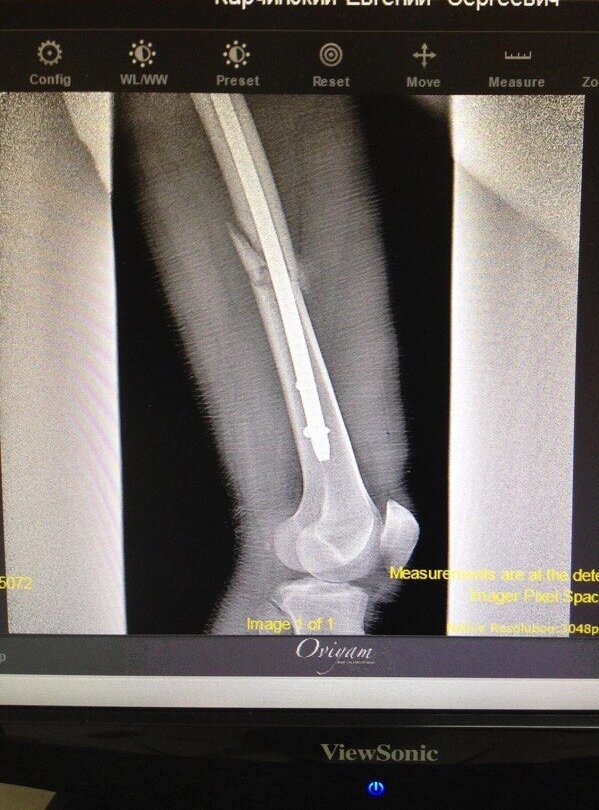

Итак, конец мая 2015. Мужа доставляют в больницу города Сочи с переломом бедренной кости. По факту удар был довольно локальный и кусок кости просто выбило. Такое собирается на штырь, сказали врачи, и на вторые сутки после операции начинаешь ходить. Ни тебе гипса, ни аппаратов каких то, ни спиц. Но, разумеется, врачами было предложено два варианта штыря, которые имели разную стоимость, что называется по хуже и неимоверно прекрасный! Короче, почти все что муж заработал он отдал за установку титанового штыря себе в ногу🤦🏼‍♀️ как и было сказано врачами через два дня он встал на ноги и с помощью костыликов стал ходить. В больницах Сочи долго не держат, там врачи собаку съели на этих переломах и там просто конвейер подобных случаев.

К сожалению, фото перелома нет, но есть фото рентгена после установки конструкции.

Красиво, да? Как ничего и не было...